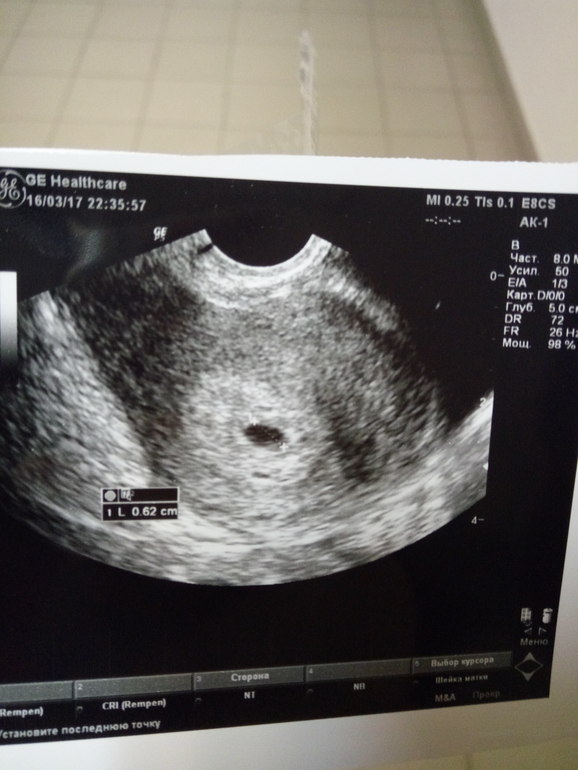

Девочки, привет) не выдержала, сходила на УЗИ. По месячным 6 неделя пошла, на УЗИ 5. Сказали угроз нет, эндометрий хороший. Фото под кат